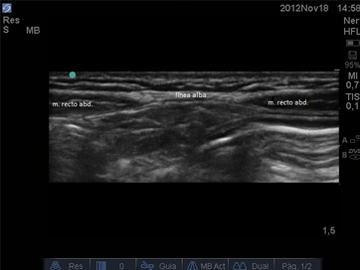

Ultrasonido de pared abdominal e inguinal